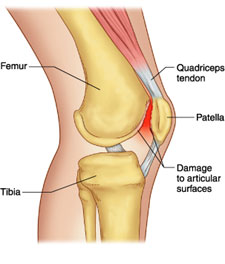

Chondromalacia patellae occurs when the tissue, known as cartilage, on the back of the knee cap (patella) is getting worn out and broken down since it is rubbing against the thigh bone (femur) that lies underneath the knee cap. The rubbing of the cartilage results in an irritated cartilage, and this is the main cause of the pain reported.

It is quite simple actually. The knee cap usually sits on the front of your knee joint, and as you bend and straighten your knee, the patella glides up and down. The movement of the patella is controlled by your thigh muscles (quadriceps) and the patellar tendon, which attaches the knee cap to the shin bone.

Pain begins when the knee cap does not move properly in its correct position and starts to rub on different parts of the thigh bone underneath causing cartilage irritation.